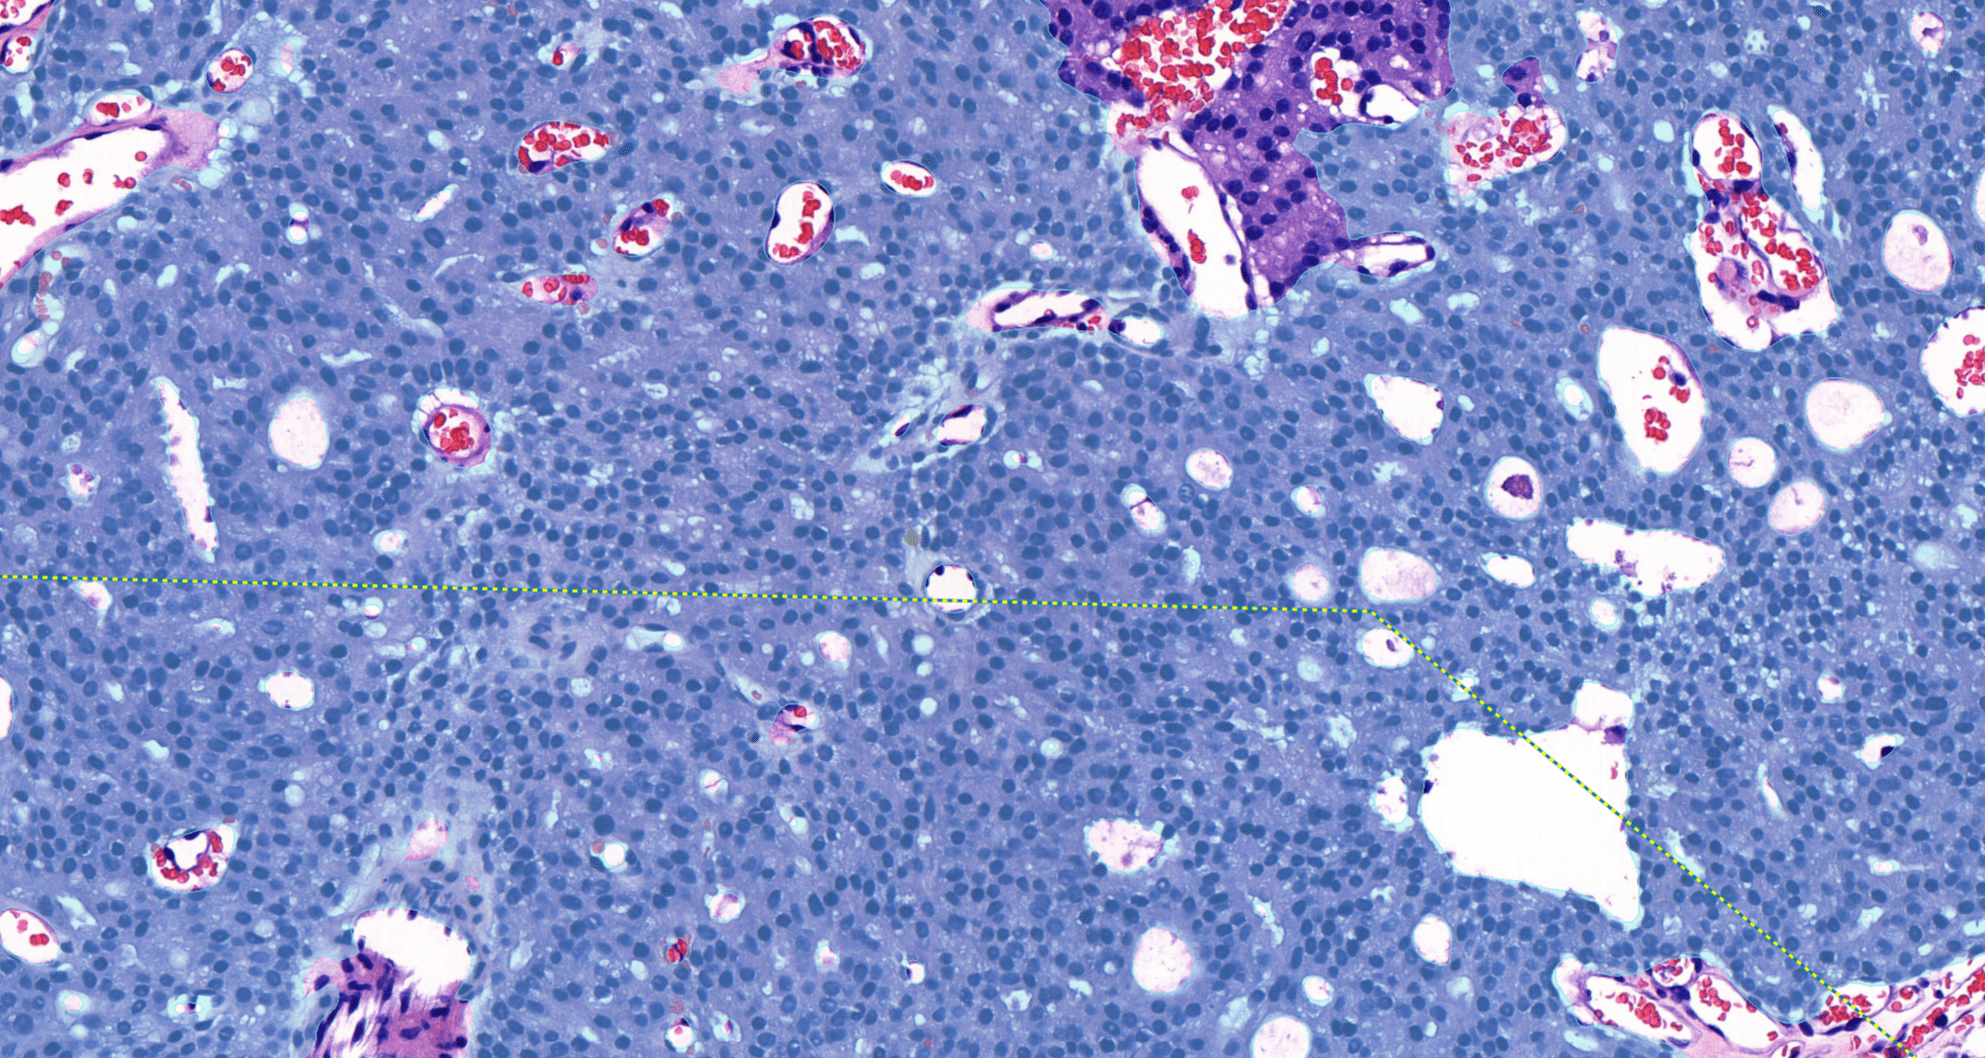

Aiforia® Prostate Cancer Suite consists of AI models with an optimized interactive user interface that supports pathologists in Gleason grade grouping and identifying adverse histopathological features.